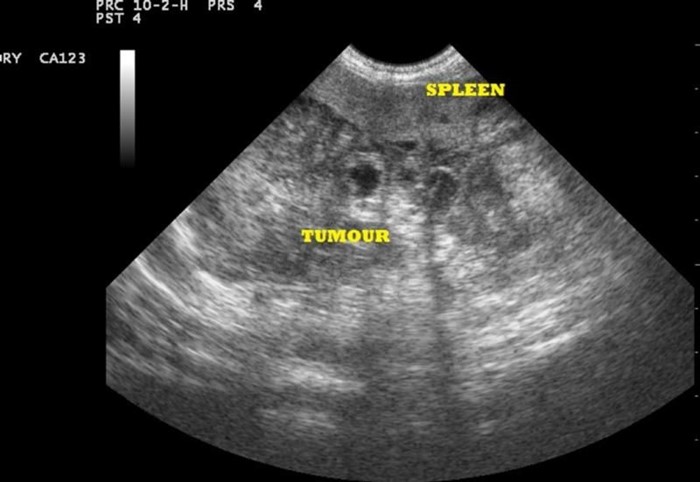

На представленном изображении можно увидеть раковую опухоль поджелудочной железы (обозначена как «tumour»).

За последние десятилетия в нашей стране наблюдается почти четырехкратное увеличение случаев рака поджелудочной железы. Наиболее распространенными симптомами этого заболевания являются пожелтение кожи и слизистых оболочек, боли в верхней части живота и необъяснимое снижение веса. В 70% случаев опухоль локализуется в головке поджелудочной железы.

О раке поджелудочной железы могут свидетельствовать следующие эхографические признаки:

- наличие очагового образования в одном из отделов железы, чаще всего гипоэхогенного или смешанной эхогенности, с темным ободком по краям,

- образование обычно хорошо визуализируется и имеет четкие контуры,

- наблюдается деформация внешнего контура самой железы,

- расширение Вирсунгова протока и холедоха,

- увеличение соседних лимфатических узлов,

- метастазы в печени выявляются в 30% случаев.